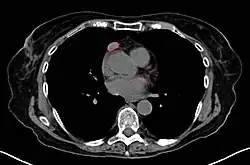

When a thymoma is suspected, a CT/CAT scan is generally performed to estimate the size and extent of the tumor, and the lesion is sampled with a CT-guided needle biopsy. Increased vascular enhancement on CT scans can be indicative of malignancy, as can be pleural deposits.[2] Limited biopsies are associated with a very small risk of pneumomediastinum or mediastinitis and an even-lower risk of damaging the heart or large blood vessels. Sometimes thymoma metastasize for instance to the abdomen.[6]

Gallery

A locally invasive circumscribed thymoma (mixed lymphocytic and epithelial, mixed polygonal and spindle). -